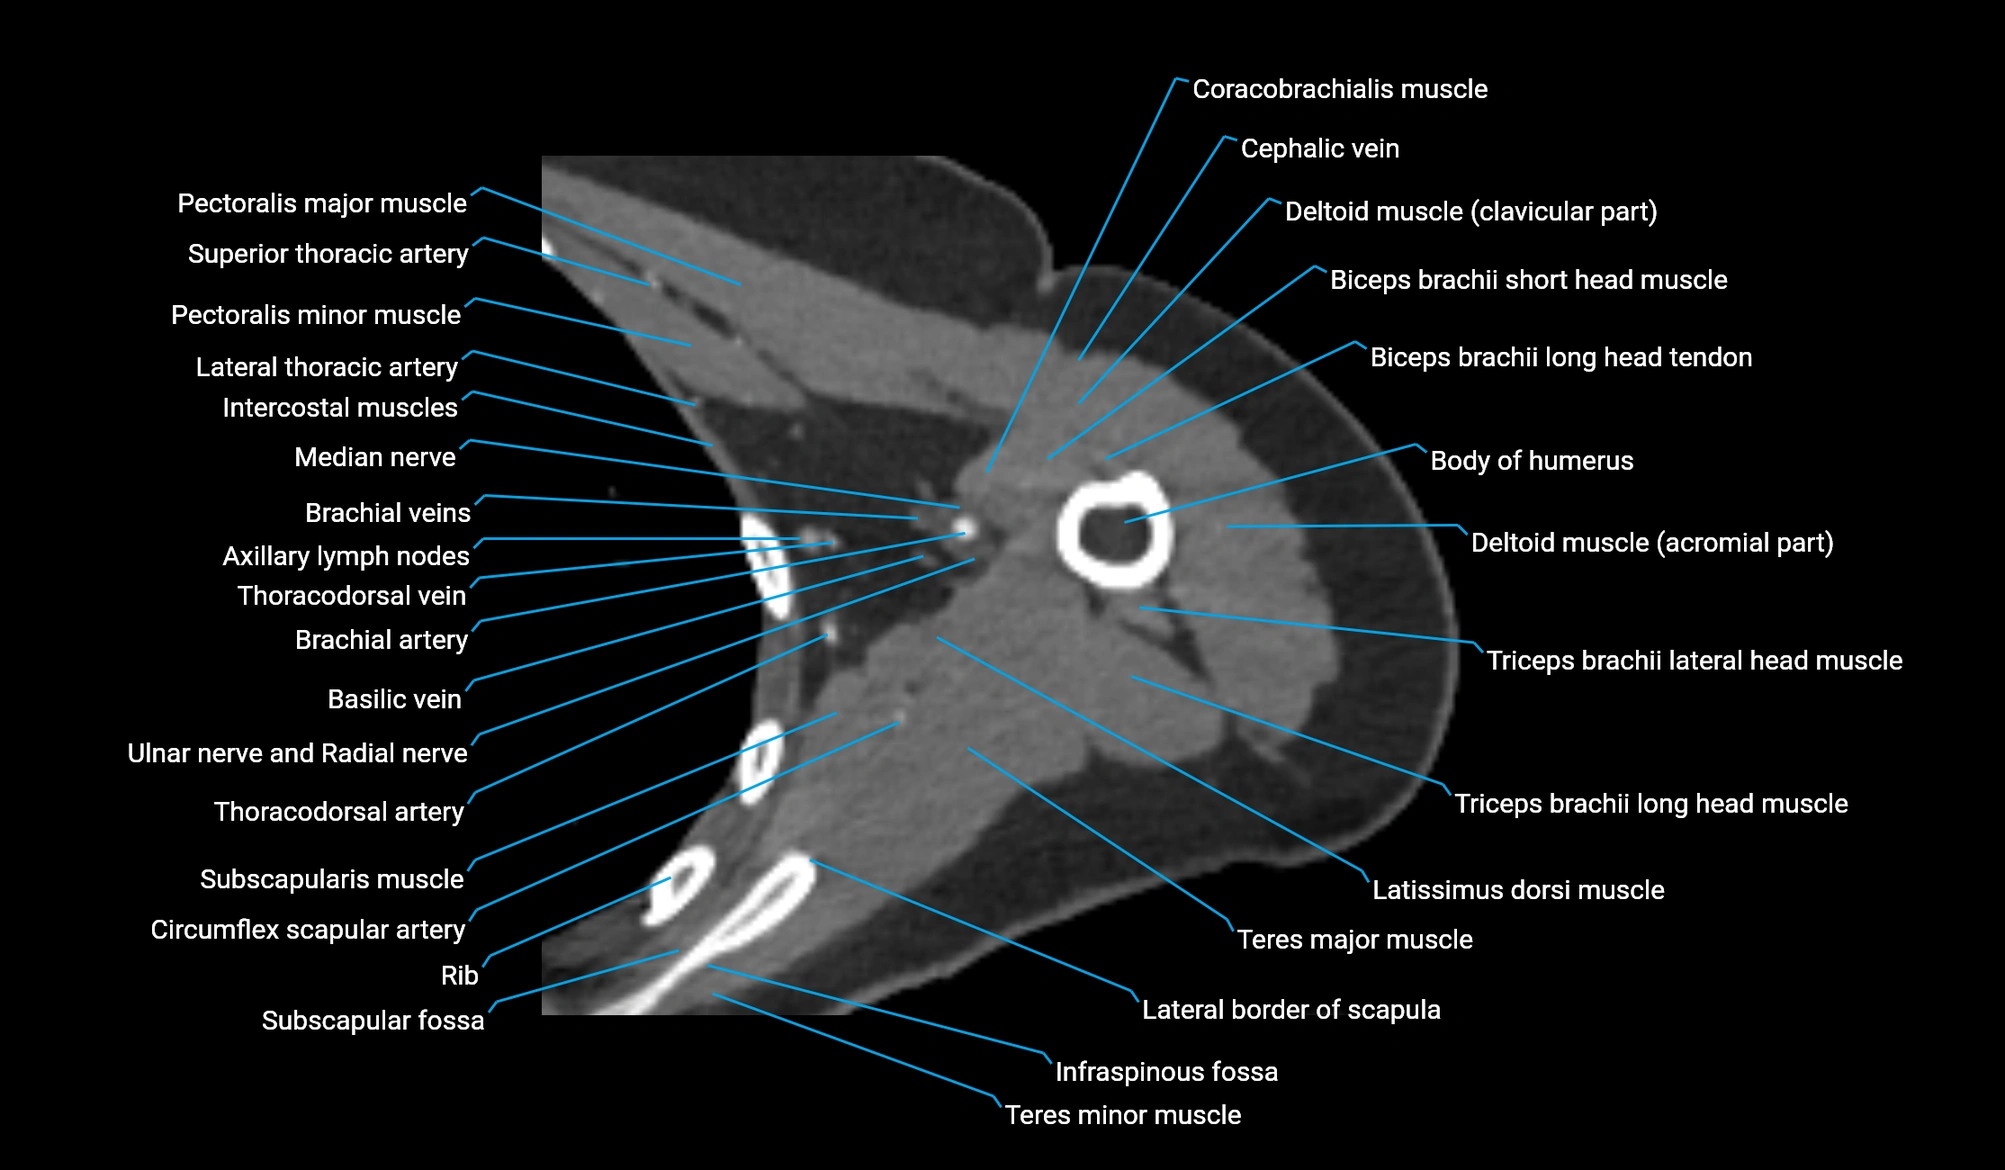

- Axillary lymph nodes

- Basilic vein

- Biceps brachii muscle

- Body of humerus

- Brachial artery

- Cephalic vein

- Circumflex scapular artery

- Clavicular part of deltoid muscle

- Coracobrachialis muscle

- Deltoid muscle

- Infraspinous fossa

- Lateral border of scapula

- Lateral head of triceps brachii muscle

- Long head of triceps brachii muscle

- Median nerve

- Pectoralis major muscle

- Pectoralis minor muscle

- Subscapular fossa

- Subscapularis muscle

- Superior ulnar collateral artery

- Teres major muscle

- Teres minor muscle

- Thoracodorsal artery

- Ulnar nerve